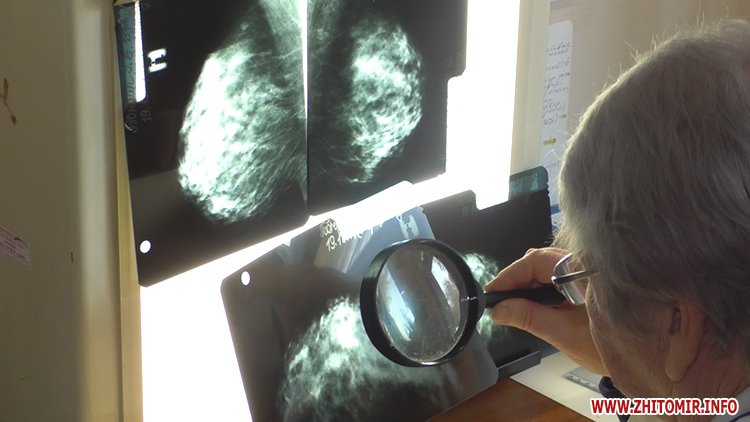

Медики кажуть: в обласному онкодиспансері можна отримати весь спектр лікування молочної залози: хіміотерапію, хірургічне, радіологічне лікування. Ба більше обстеження безкоштовні, заплатити доведеться за мамографію. Так як, плівка для знімка коштує близько 150 гривень. Рентгенолог пані Людмила показує як працює мамограф та роз’яснює задля чого робить знімки під різними кутами.

«Це права - пряма, як лягають груди, а це косі знімки. Виводяться грудний м’яз разом з лімфовузлами і ми бачимо чи вони збільшені, чи ні. І, патологія, яка не увійшла у прямому знімку, ми гарно бачимо на косих знімках», - пояснює лікар-рентгенолог Житомирського обласного онкологічного диспансеру Людмила Ясакова.